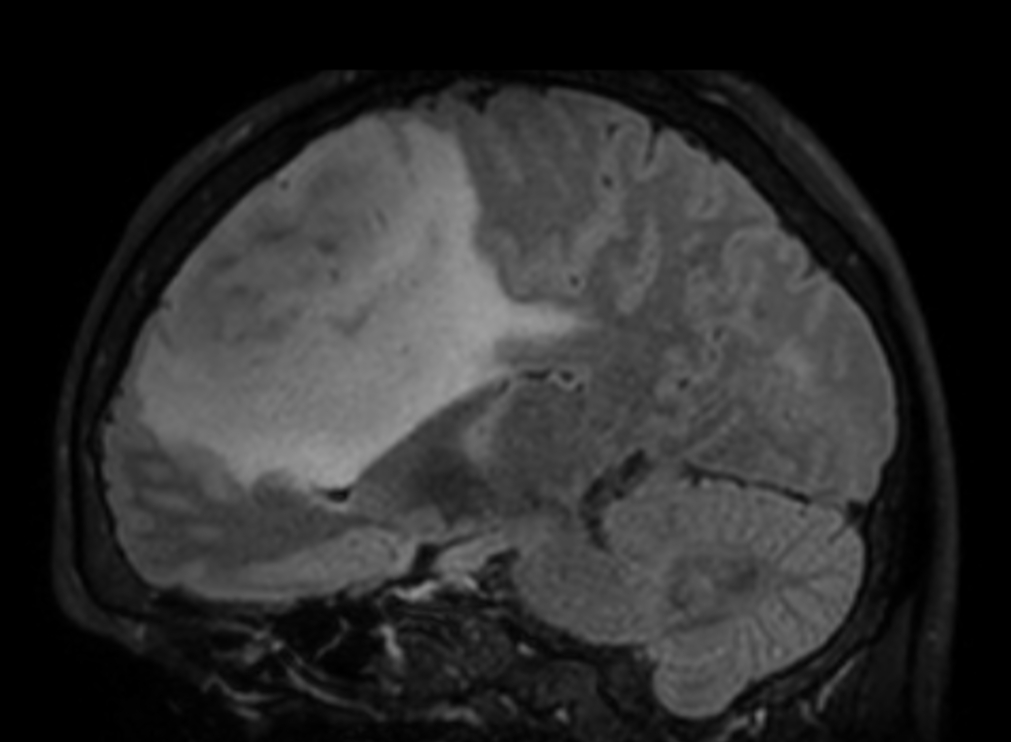

3D VIEW - T2w FLAIR (sagittal reformat)